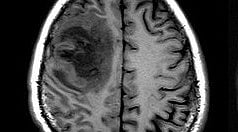

MSA is an adult-onset sporadic disorder characterized by an abnormal buildup of α-synuclein protein, similar to Parkinson’s disease and Lewy body dementia. However, due to its rarity and variability in symptoms, MSA remains poorly understood.

In addition to genome analysis, the researchers conducted cell-type specific transcript expression analysis to understand the potential impact of genomic changes on specific cell types, such as neurons and oligodendrocytes. This analysis revealed that defects within oligodendrocytes may play a significant role in MSA pathogenesis as a primary oligodendropathy.